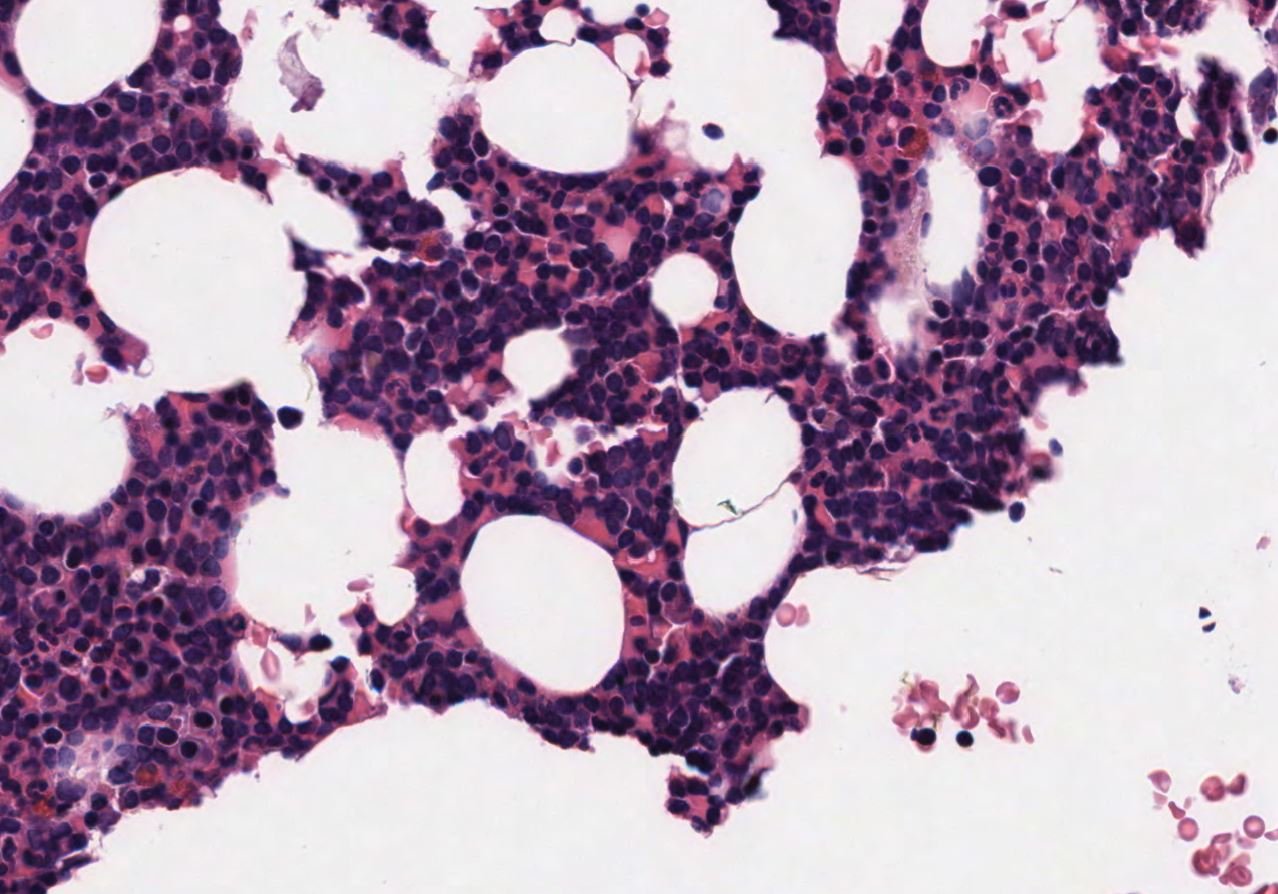

Case: BoneMarrow